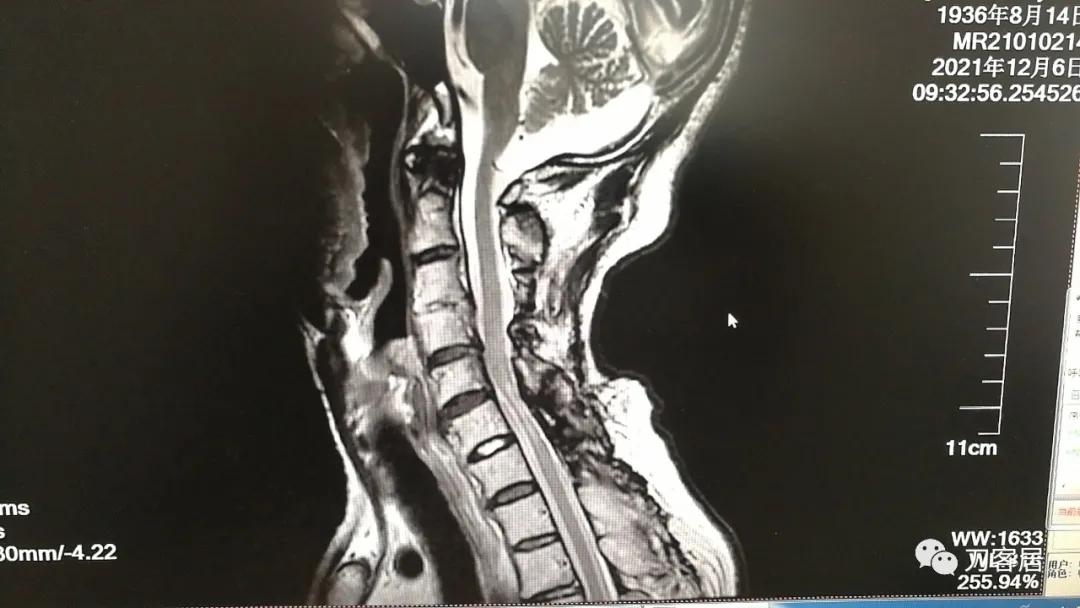

图23. 2021年12月6日复查颈椎MRI-2,提示颈5-7平面椎管狭窄,脊髓动态受压,脊髓信号改变。

图24. 2021年12月6日复查颈椎MRI-2,提示颈5-7平面椎管狭窄,脊髓动态受压,脊髓信号改变。片子显示患者为1936年生,那么现在的年龄应该是接近86岁了。

从这两张颈椎MRI片子来看,颈3-4椎体分节不全,颈2-5椎管成形手术减压很好,椎管无狭窄,脊髓后移,颈5-7椎管有狭窄,脊髓信号改变。此信号改变可能系脊髓萎缩,也可能是头段脊髓后移后,颈5-6节段后方椎板仍在,椎管相对狭窄,脊髓受压。